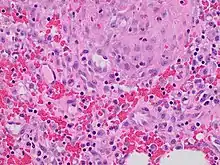

Granulation tissue is new connective tissue and microscopic blood vessels that form on the surfaces of a wound during the healing process.[1] Granulation tissue typically grows from the base of a wound and is able to fill wounds of almost any size. Examples of granulation tissue can be seen in pyogenic granulomas and pulp polyps. Its histological appearance is characterized by proliferation of fibroblasts and thin-walled, delicate capillaries (angiogenesis), and infiltrated inflammatory cells in a loose extracellular matrix.

Granulation tissue is composed of tissue matrix supporting a variety of cell types, most of which can be associated with one of the following functions:

The main immune cells active in the tissue are macrophages and neutrophils, although other leukocytes are also present. These work to phagocytize old or damaged tissue, and protect the healing tissue from pathogenic infection. This is necessary both to aid the healing process and to protect against invading pathogens, as the wound often does not have an effective skin barrier to act as a first line of defense.

It is necessary for a network of blood vessels to be established as soon as possible to provide the growing tissue with nutrients, to take away cellular wastes, and transport new leukocytes to the area. Fibroblasts, the main cells that deposit granulation tissue, depend on oxygen to proliferate and lay down the new extracellular matrix.

In vascularisation, also called angiogenesis, endothelial cells quickly grow into the tissue from older, intact blood vessels. These branch out in a systematic way, forming anastomoses with other vessels.